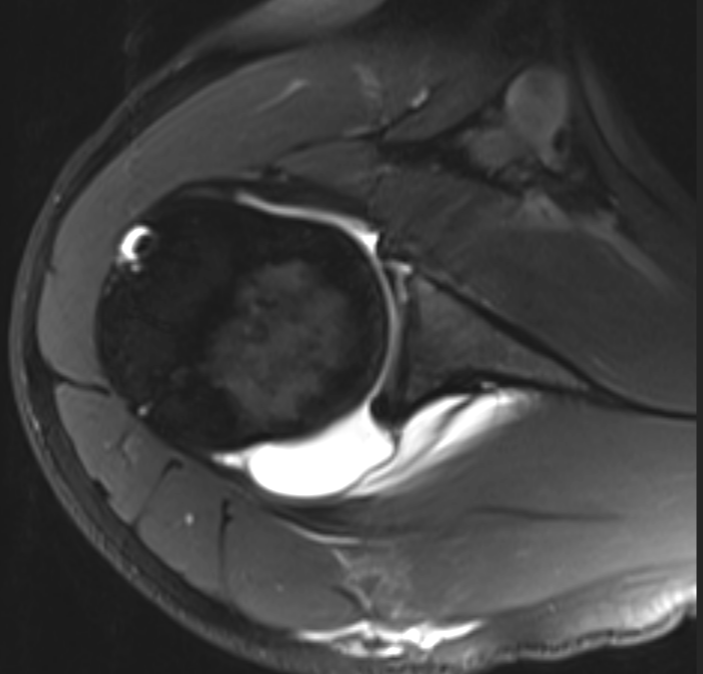

GLAD (glenolabral articular disruption) lesion